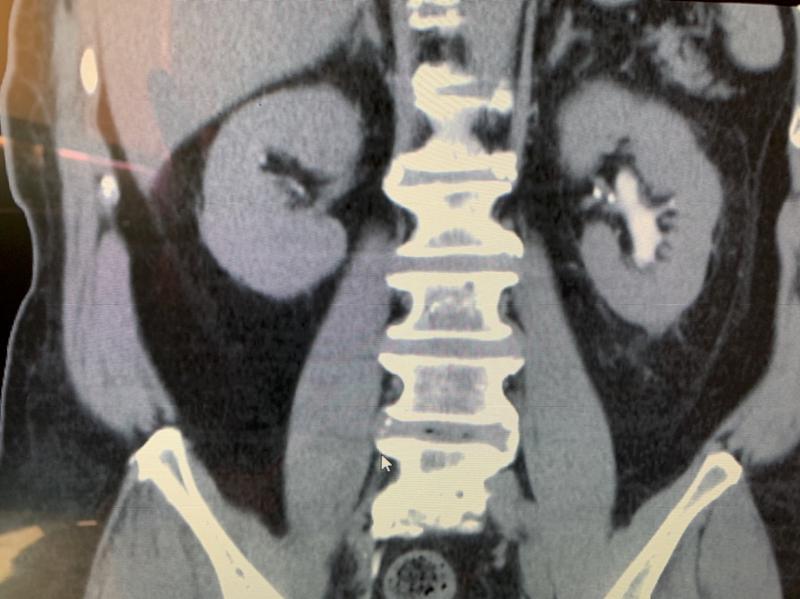

高市68歲江姓清潔品男加工員106年因腎臟癌切除左腎,108年確診膀胱癌接受內視鏡手術搭配化療,先後罹患兩癌影響性功能,即使觀賞成人影片助興也力不從心,求助阮綜合醫院泌尿科主任蔡秉儒,開立男性荷爾蒙搭配壯陽藥治療,總算重振男性雄風。另名70歲金姓男骨董商患有糖尿病痼疾,108年確診帕金森氏症定期服用神經科藥物,意外發現攝護腺肥大影響排尿,衍生性功能障礙問題,經蔡秉儒開立男性荷爾蒙搭配壯陽藥治療逐漸獲得改善,與妻子重修舊好,再享魚水之歡。

蔡秉儒表示,根據多數研究,膀胱癌肇因長期吸菸或曾接觸化學物質,可能出現血尿、頻尿急尿、噁心食慾差等症狀,甚至影響性功能,攝護腺肥大衍生頻尿、夜尿、尿量少、排尿困難等,嚴重造成性功能障礙,如有以上情況最好求助專業醫師,並依指示配合用藥,勿聽信偏方及濫用成藥,維護自身健康。圖/阮綜合醫院提供、文/高培德